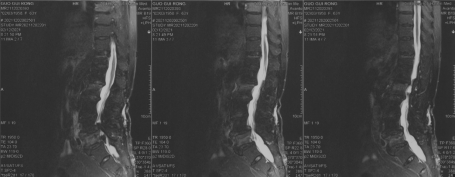

腰椎核磁可见第二腰椎、第五腰椎骨折合并椎管狭窄

腰椎CT、核磁可见腰4-5椎管狭窄